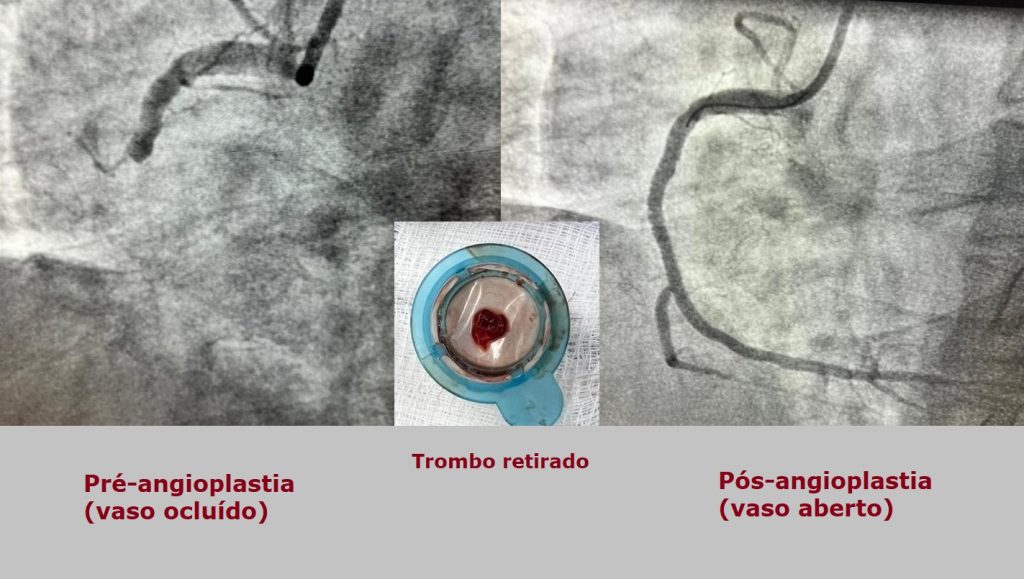

TAVI - Implante percutâneo de válvula aórtica

Cirurgia minimamente invasiva para tratamento de estenose aórtica grave em pacientes de alto risco para a cirurgia convencional ("peito aberto"). O procedimento consiste no implante por catéter de uma nova válvula sobre a válvula doente do paciente, comprimindo os folhetos degenerados entre a estrutura da válvula protética e a parede da aorta.